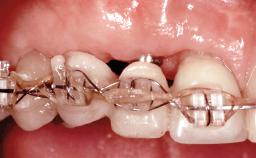

Replacement of Four Incisors with a Fixed Partial Denture on Two Narrow-Neck Implants after Implant Failure

| Prosthesis Type | FDP |

| Retention | Screw-retained, with splinted implants Screw-retained, with splinted implants |

| Provisional Implant-Supported Prosthesis | Prosthodontic margin >3 mm apical to mucosal crest Prosthodontic margin >3 mm apical to mucosal crest |

| Interim Prosthesis during Healing | Removable Removable |